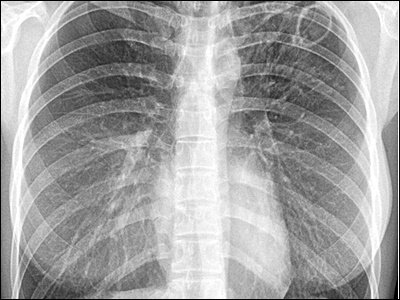

결핵 진단을 위해서는 피부 검사, 가슴 X-선, 결핵균 검사 등의 검사가 필요합니다. 이러한 검사를 통해 정확한 진단을 받을 수 있습니다.